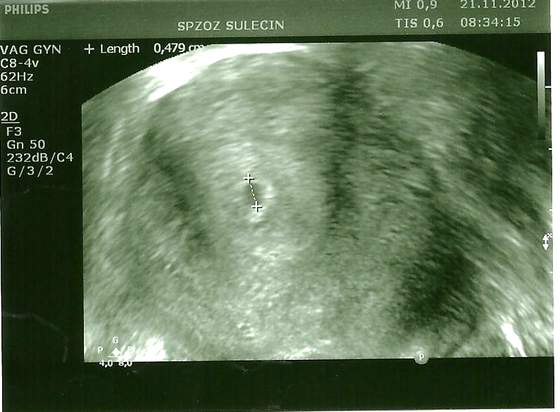

już jestem po, pęcherzyk ciążowy umiejscowiony prawidłowo, według lekarza wielkość odpowiada równo skończonemu 4 tygodniowi, czyli jestem w piątym, lekarz kazał się oszczędzać, pracować mogę, bo na tym etapie to nic nie zmieni, następna wizyta 5tego grudnia po południu i będziemy patrzeć czy jest dzidziuś czy bije serduszko, jestem szczęśliwa ale i przerażona, dużo wątpliwości: czy w pęcherzyku rozwinie się płód czy będzie serce.... ehhh

ale lekarz powiedział że rozumie mnie i że po poronieniu będę miała ogrom obaw dopóki nie wezmę dziecka w ramiona dwa razy więcej na pewno niż normalnie, a i żartował z mężem, że najpierw chcą a potem gadają że umrą że coś ty mi zrobił hahahah tak sobie stali i gadali a mój jak zobaczył zdjęcie usg to oczy mu się tak zeszkliły że szok, teraz siedzę w pracy dostałam luteinę znowu i będę ją brać i brać hihihi pewnie do 12 tygodnia przynajmniej, to chwalę się moim cudem

Załączniki

• 4 tydzień 001.jpg

4 tydzień 001.jpg

29 KB · Wyświetleń: 37